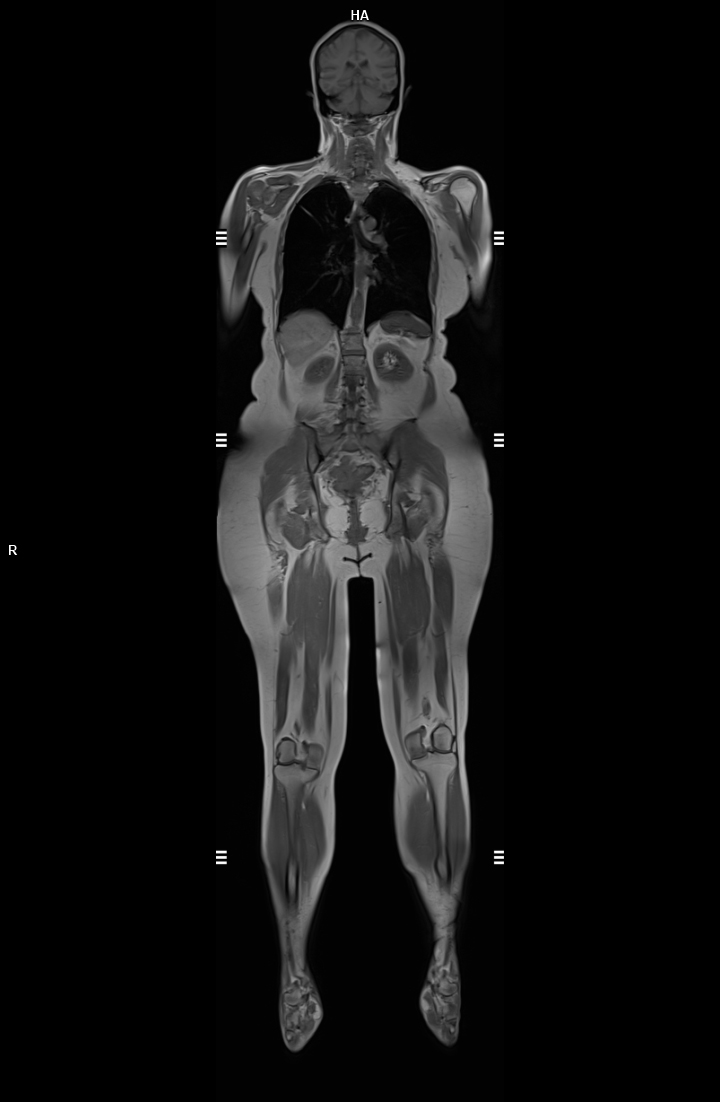

-Obez hastalar için avantajlıdır 👉 Geniş yapısı sayesinde yüksek kilolu hastalarda kullanılabilir.